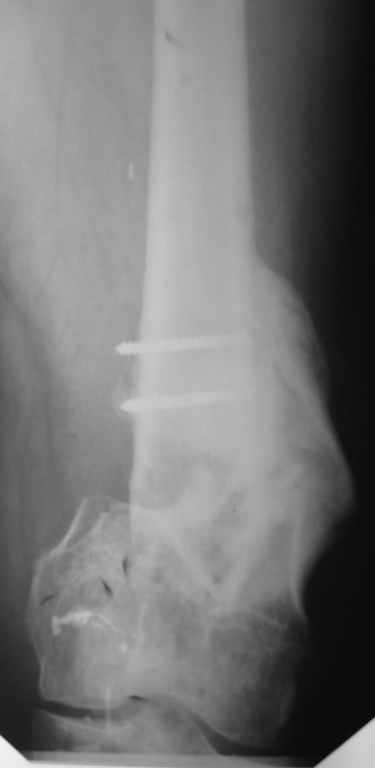

Был оперирован, среди прочего - остеосинтез DHS-фиксатором чреcшеечного перелома правого бедра, DCS-фиксатором остеосинтез оскольчатого чрезмыщелкового перелома левого бедра. Однако, в связи с развитием гнойного коксита были вынуждены убрать DHS-фиксатор и головку. Гнойный свищ правого тазобедренного сустава закрылся сразу после операции. Из-за вторичного смещения и поломки винтов пришлось удалить DCS-фиксатор и сращивать левое бедро внешней иммобилизацией. Прошло чуть более года. Пациент ходит с опорой на обе ноги,пользуется палочкой. Справа относительное укорочение 3см. Слева варус 33гр., тугой ложный сустав н/3бедра. Движения в коленных суставах почти в полном объёме.Перед нами встали вопросы, с чего начать? Протезирование правого ТБС? Восстановление опорности левой конечности? Воспользоваться-ли для этого интрамдулярным остеосинтезом гвоздём с блокированием с ретроградным введением? Стараться при этом восстановить полностью длину, или оставить на потом, на аппаратное решение? Или сразу попытаться использовать аппарат Илизарова? Но боимся потерять колено? Вопросов много.С благодарностью выслушаем все мнения.Заранее спасибоРахматуллин Ринат НургаяновичГКБ N 13 г.Уфа.

Если пытаться одномоментно и ретроградно - пробовали, закрыто так мобилизовать ложный сустав, чтобы восстановить ось и длину - нереально. А если все мобилизовать открыто, потеряем преимущества закрытого штифтования, да и обширная околуставная рана функции не способствует.

Впрочем, все равно придется через небольшой разрез убирать обломки винтов, лучше воспользоваться специальными инструментами (если нет - корончатая фреза + втулка с резьбой и стопором, спросить в "Деосте"). Востановить аппаратом недели за 2 длину и ось. И вторым этапом перейти на интрамедуллярный остеосинтез. Причем можно и анте-, а не ретроградный. Если в аппарате все уже стоит ровно - это обычно довольно гладкая и предсказуемая процедура. Ну и тут же перейти на эндопротез. Если что-то не так, протез можно и позже, когда полностью восстановится опороспособность левой ноги.